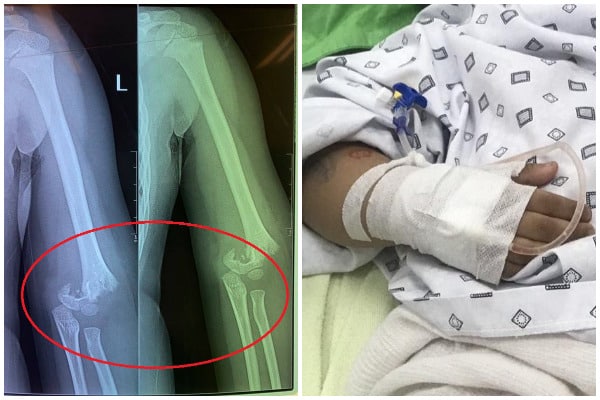

Hà Nội: Bé gái 5 tuổi ngã gãy tay trong giờ học, nguy cơ bị liệt

Bé N.B.P. (5 tuổi) bị gãy tay trong giờ học tại Trường Mầm non Vườn trẻ thơ (Hai Bà Trưng, Hà Nội).